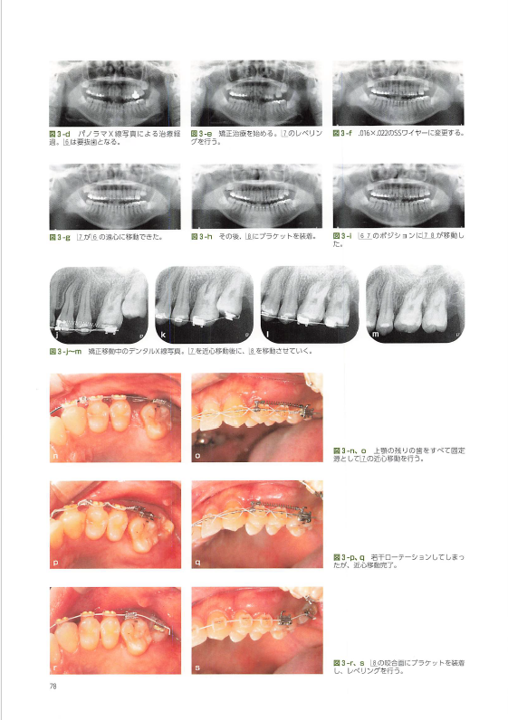

ニーズ3:40代以降で「歯周病が進行」している場合の矯正

40代~60代の方が矯正治療を希望されることも最近は増えてきました。お口の状態に問題がない場合は通常の矯正治療を行いますが、この年齢になると多くの方が「歯周病」になっていることが多くあります。歯周病の状態のまま矯正治療をすると矯正治療はうまくいかないため、まずは歯周病を改善してから治療を開始します。

また、歯周病の進行がかなり進行している場合、見た目も悪化しているため、そのまま矯正治療を行ったとしてもキレイにならないことがあります。そこで当院では、歯周病と矯正治療の他、セラミックの被せ物やケースによってはインプラントを併用し、お口全体の審美性を回復させる治療も行っています。

この総合的な治療を行うことで、口元が綺麗になる他、歯周病の再発防止(歯周ポケットを浅くする)、適切な噛み合わせの調整も可能になるため、お口全体の健康にもつながります。

このような治療は、当院の担当医である理事長はとても得意としています。このケースに関して、海外での発表や書籍の執筆も行っています。